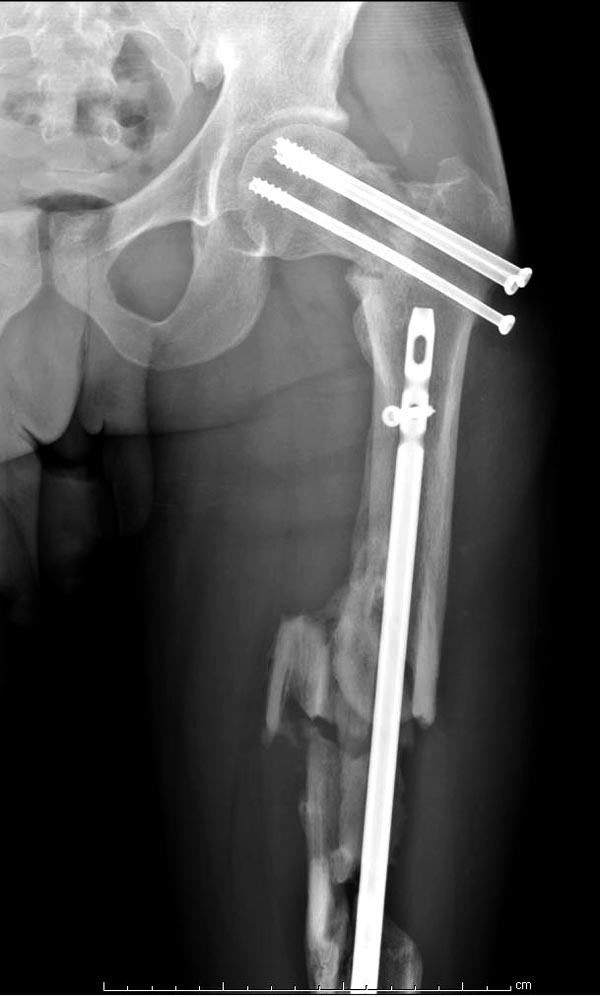

Здесь выставлен ренгенограммы больного, ему 21, травму получил в результате высокоскоростной погони на украденной машине, которая закончилась смертью трех остальных “боевых комрадов”. Начатую коллегой открытую операцию на шейке пришлось закончить мне, установкой винтов и ретроградной фиксацией бедра. Выписка в обычное сроки и наблюдался амбулаторно. Каждый раз напоминали о возможности осложнений ввиде несращения! По истечению 4 месяцев появились признаки варусной деформации. На СТ срезах несращение шейки и бедра. Риминг, замена на более толстый гвоздь и вальгусная остеотомия.

И вопрос по представленному вами случаю - перелом шейки вроде как латеральный, почему остеосинтез винтами? Несращение и варус - закономерный результат?